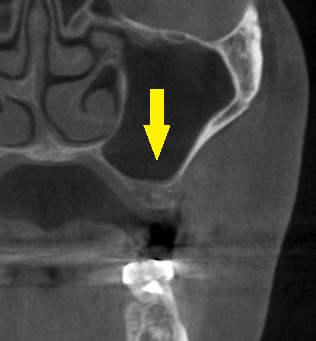

本日、同部に直径6mm、長さ8.5mmのワイドインプラントを埋入しました。

下の写真下段が手術後のCTです。